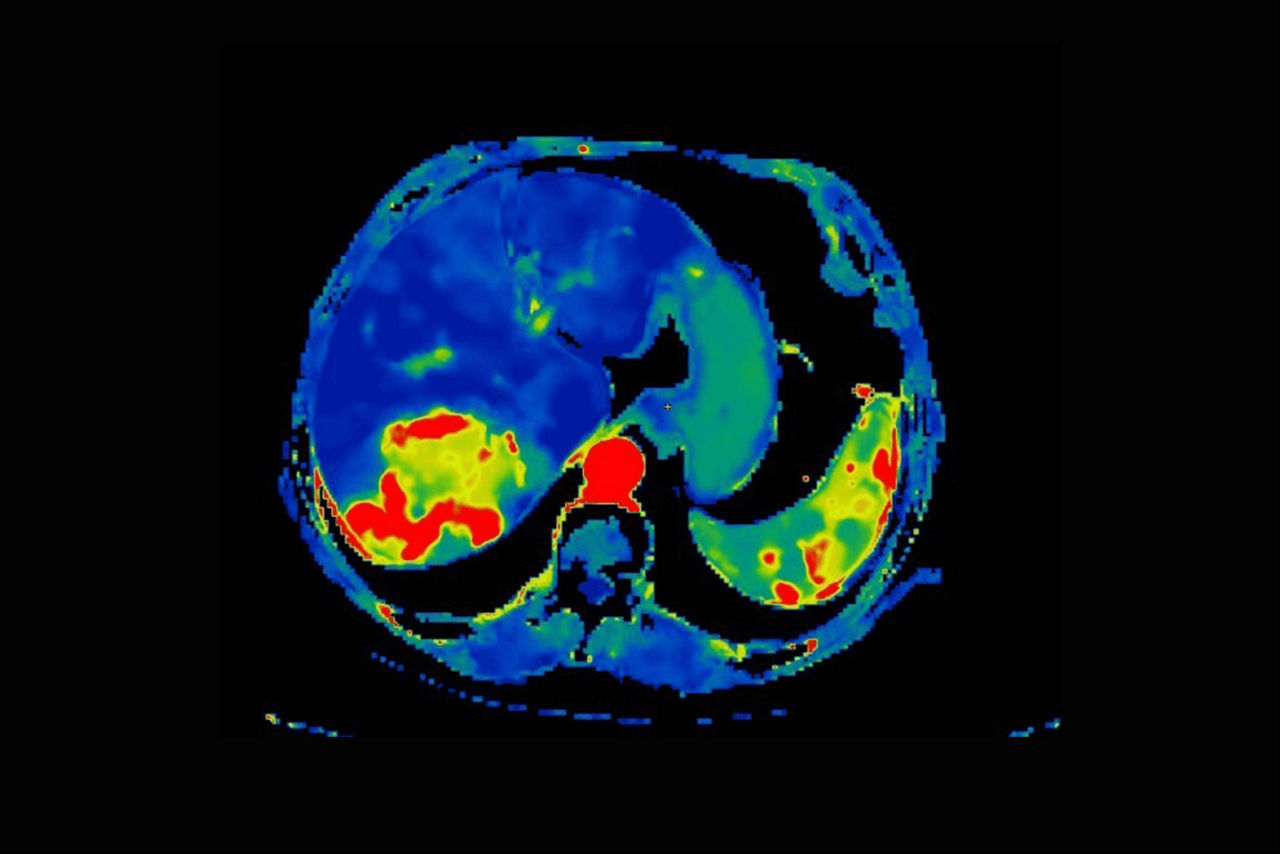

CT Body Tumor Protocol

• Automatically produces functional maps once the user selects an artery using a simple and intuitive workflow

• Leverages most of the advanced algorithm settings that are part of the Brain Stroke protocol

• Optimized protocols for pancreas, prostate, kidney, soft tissue, spleen, bone and liver perfusion

• CT Non-Rigid Registration: Fully automated protocols used for dynamic body acquisitions to register data for use in perfusion analysis